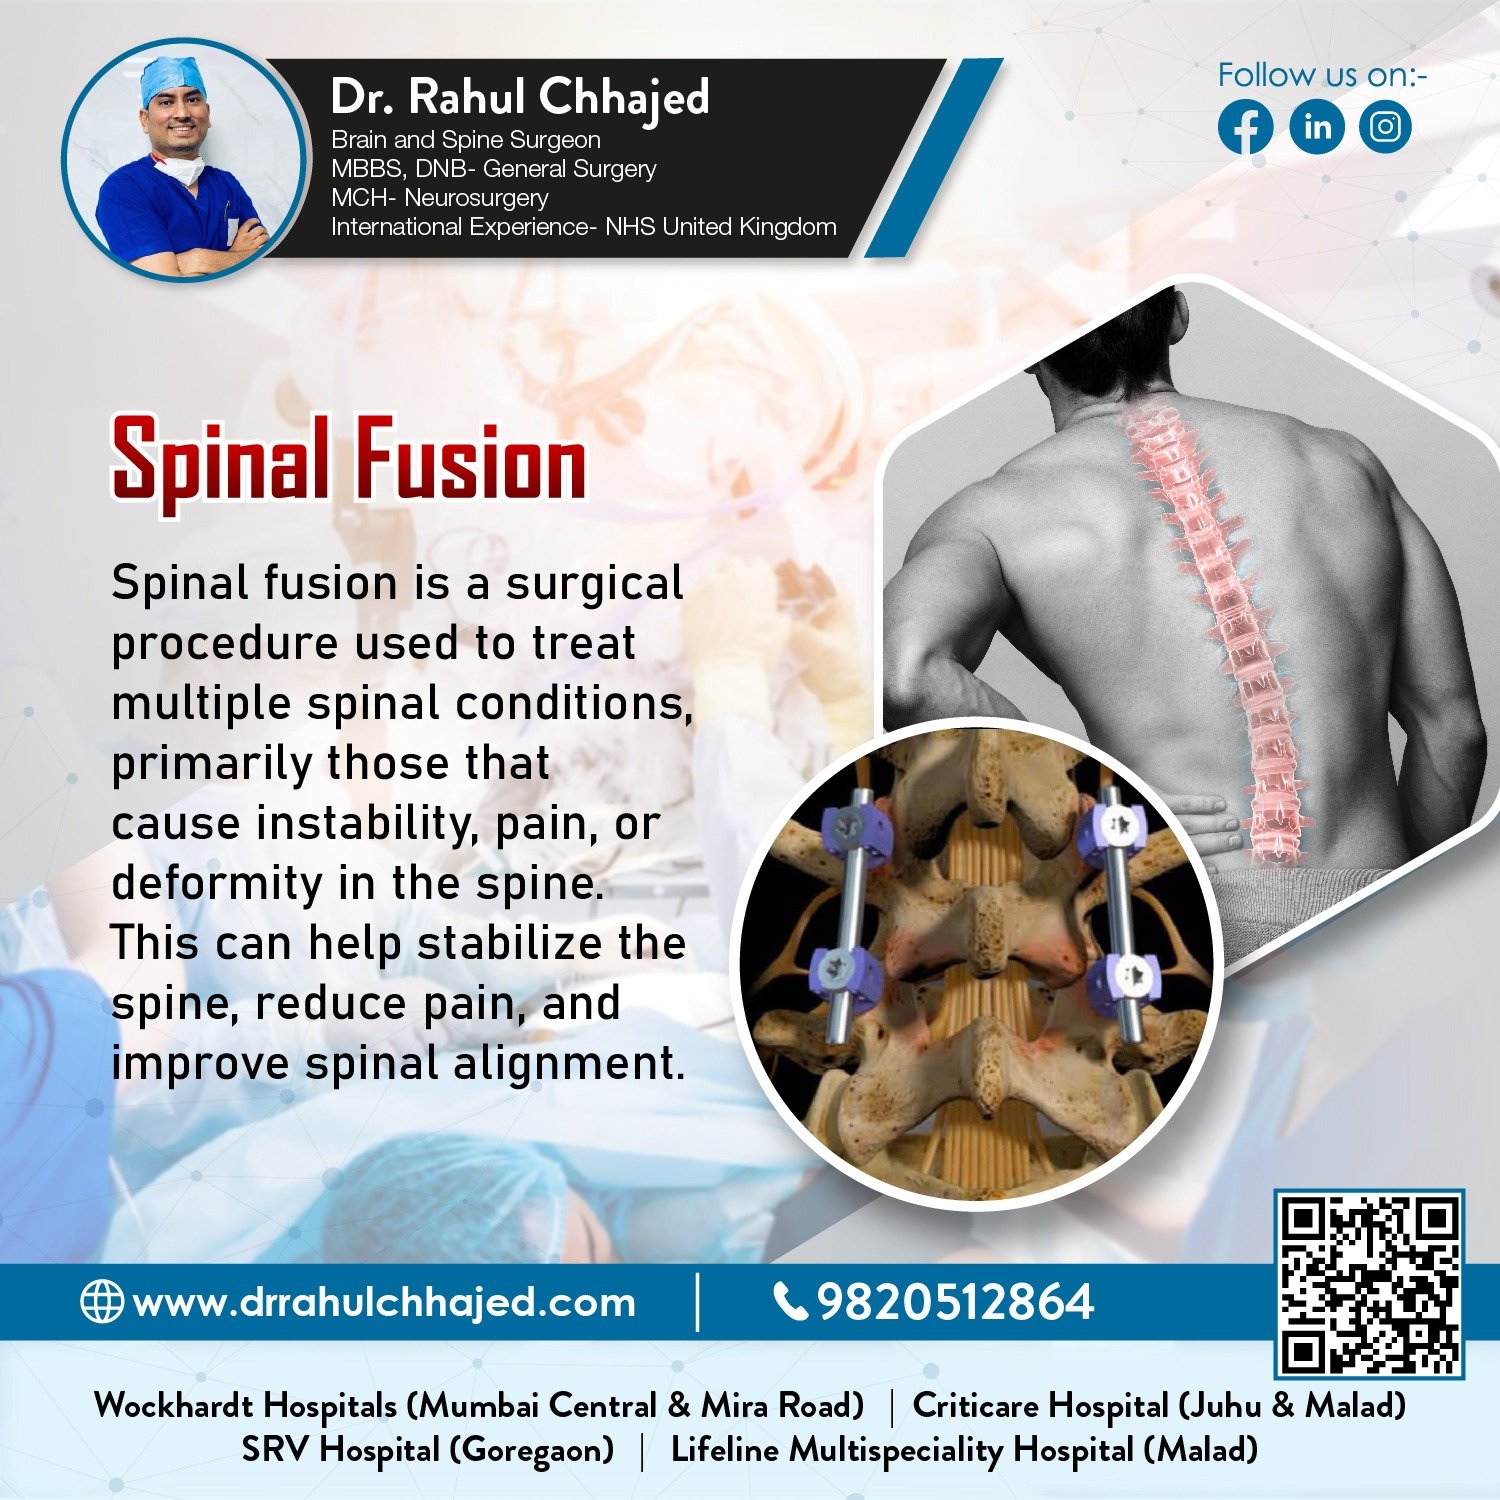

Spine Surgery

Dr. Rahul is a highly experienced spine surgeon specializing in diagnosing and treating spinal conditions. He performs a wide range of surgical options for spinal conditions, including minimally invasive techniques, spinal fusion, and disc replacement.